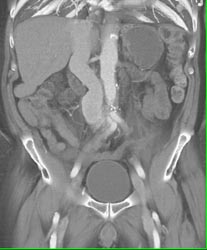

Loeys-Dietz Without Dissection